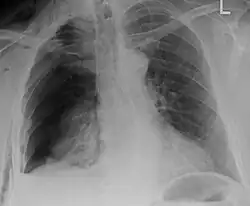

Plain X-rays often pick up displaced fractures but often miss undisplaced fractures.[13] CT scanning is generally able to pick up both types of fractures.[13]